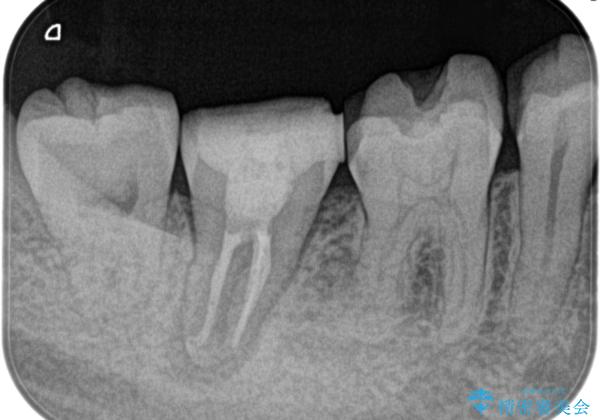

- 定期検診にて膿の出口を見つけたことを主訴に来院されました。

検査の結果、診断を歯髄壊死、症候性根尖性歯周炎とし抜髄を行っております。

根管充填はCWCTにて行なっています。